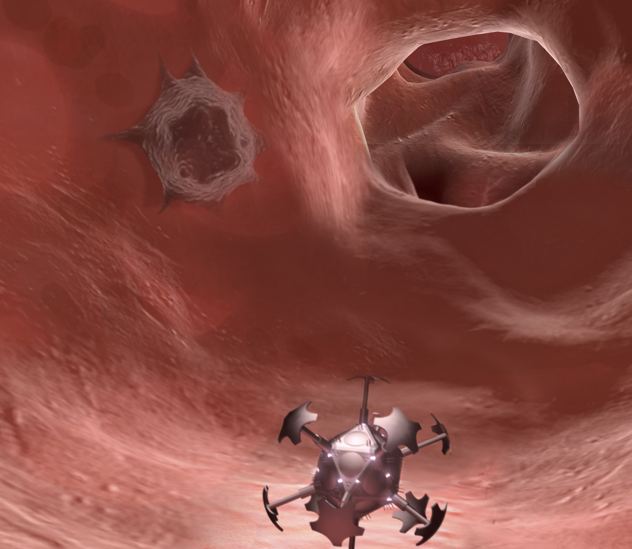

7. Thuốc Nano

Công nghệ nano trở thành nỗi ám ảnh của nhiều người vì nó có thể là nguyên nhân của ngày tận thế nhưng công nghệ này vẫn phát triển và có những bước nhảy vọt nhanh chóng.

Hiện nay y học nano cho phép cung cấp thuốc tới từng địa điểm cụ thể trong cơ thể bệnh nhân hoặc với phương pháp điều trị liên quan tới các hạt nano ở mức phân tử phát tán vào cơ thể.Một thử nghiệm điều trị ung thư phổi bằng cách sử dụng các hạt nano được hút vào phổi và cố định lại tại mọi ngóc ngách của phổi, các hạt này được kích hoạt nhiệt độ để giết chết các tế bào bệnh. Phản ứng tự nhiên của cơ thể sẽ loại bỏ các tế bào chết và các hạt nano ra bên ngoài. Phương pháp này đã thành công ở chuột nhưng chưa xóa sổ được 100% các tế bào ung thư nhưng đó vẫn là một giải pháp khá tiềm năng sau này.

Sử dụng các hạt nano có khả năng tự nhân đôi và lập trình có thể xác định mục tiêu tế bào bệnh để tiêu hủy, và xây dựng lại các tổ chức tế bào khỏe mạnh. Tât nhiên, rủi ro có thể xảy ra nếu chúng tự phá hủy cả những bộ phận không mắc bệnh dẫn tới cơ thể bị lão hóa nhanh chóng. Cái đáng nói ở đây chính là khả năng những thế hệ con người không bao giờ mắc bệnh và già yếu sẽ sớm xuất hiện trên Trái Đất.